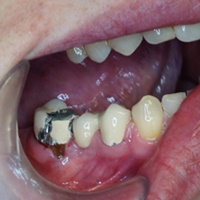

Dziesieć lat po wykonaniu mostu pacjent zgłosił się z recesją dziąsła i próchnicą korzenia. Zamiast ekstrakcji wykonano hemisekcję i nowy most.